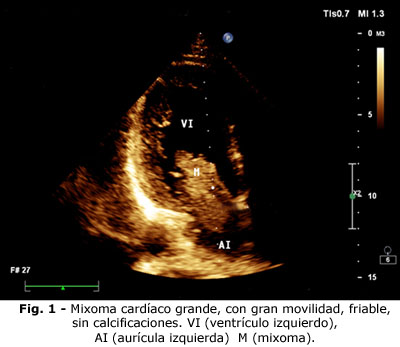

A los 6 meses de tratamiento, incluyendo rehabilitación integral, continúa con malestar general, decaimiento, dolores articulares, fiebre, cefalea, dolor torácico tipo ángor, disnea al esfuerzo, ortopnea, palpitaciones y mareos, que el paciente describe como sensación de muerte. Acude a consulta de cardiología, se constata soplo diastólico largo y plof diastólico. Se realiza ecocardiograma de urgencia, en el cual además de la hipertrofia concéntrica moderada y discreta disfunción diastólica, presentaba un mixoma cardiaco grande que bascula desde la aurícula izquierda (AI) hacia el ventrículo izquierdo (VI), con gran movilidad, por un pedículo largo que le permitía estar más tiempo en el ventrículo izquierdo que en la aurícula izquierda. Tenía aspecto friable, y a pesar de que la válvula mitral permanecía sana, le ocasionaba enclavamiento en el orificio valvular, con dificultad para el paso de la sangre en diástole, de la AI al VI.

Se le realizaron estudios hemodinámicos, la coronariografía fue normal, sin lesión valvular mitral. Se extirpó un tumor de gran tamaño. En anatomía patología se comprobó que se trataba de un tumor benigno, muy friable: mixoma con pedículo largo, que le permitía permanecer en el ventrículo izquierdo y enclavado en el orificio valvular mitral. Después de la intervención, el enfermo ha evolucionado bien, con seguimiento en consulta de cardiología y tratamiento para su hipertensión (ver Fig. 1, Fig. 2 y Fig. 3).

El tumor cardiaco primario más frecuente, es el mixoma, cuando es grande, suele ser friable, de gran movilidad y da lugar a fenómenos cardioembólicos, tanto pulmonares (cuando son derechos) y sistémicos (cuando son de cavidades izquierdas).(8,9) Cuando se diagnostica un infarto cerebral, es preciso tener en cuenta a este tumor, entre los diagnósticos diferenciales.